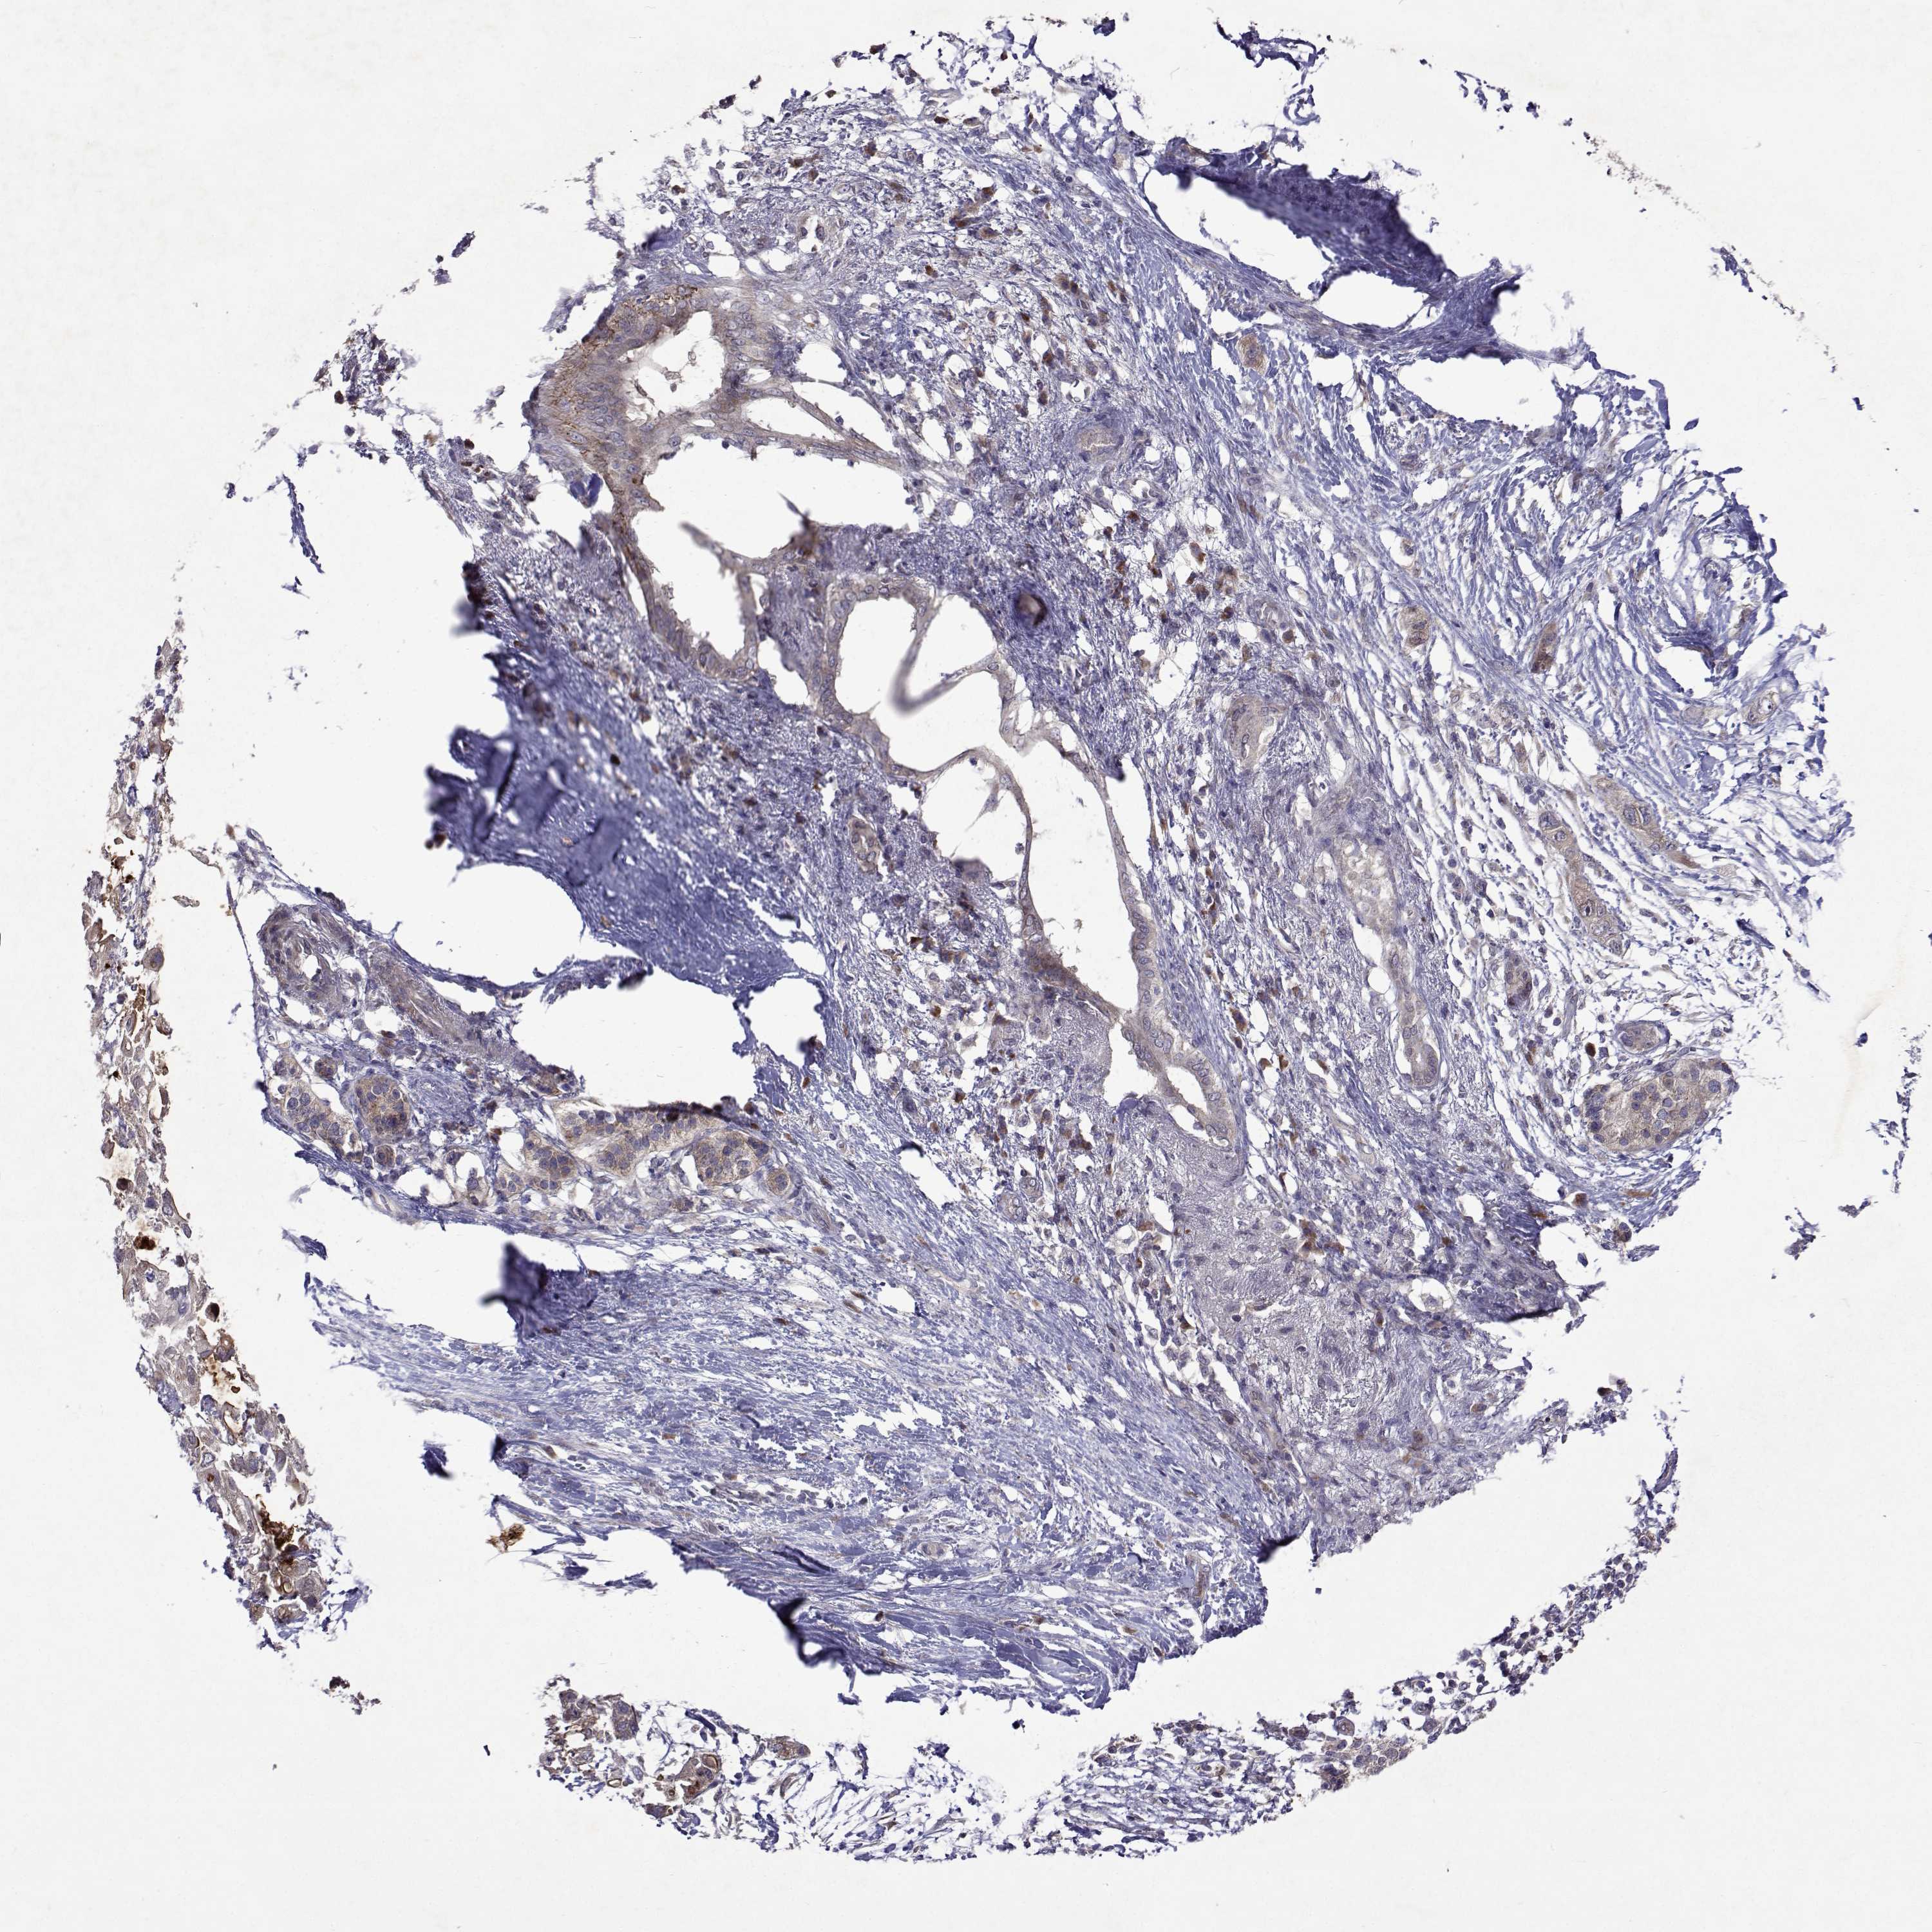

PANCREATIC CANCER - Protein expressioni

A mouse-over function shows sample information and annotation data. Click on an image to view it in a full screen mode. Samples can be filtered based on level of antibody staining by selecting one or several of the following categories: high, medium, low and not detected. The assay and annotation is described here.

Note that samples used for immunohistochemistry by the Human Protein Atlas do not correspond to samples in the TCGA dataset.

Antibody stainingi

Antibody staining in the annotated cell types in the current human tissue is reported as not detected, low, medium, or high, based on conventional immunohistochemistry profiling in selected tissues. This score is based on the combination of the staining intensity and fraction of stained cells.

Each image is clickable and will lead to virtual microscopy that enables deeper exploration of all samples and also displays staining intensity scores, fraction scores and subcellular localization as well as patient and tissue information for each sample.

Antibody HPA051181

Antibody HPA061454

Antibody CAB069406

Staining

High

Medium

Low

Not detected

Intensity

Strong

Moderate

Weak

Negative

Quantity

>75%

75%-25%

<25%

None

Location

Nuclear

Cytoplasmic/membranous

Cytoplasmic/membranous,nuclear

Adenocarcinoma, NOS